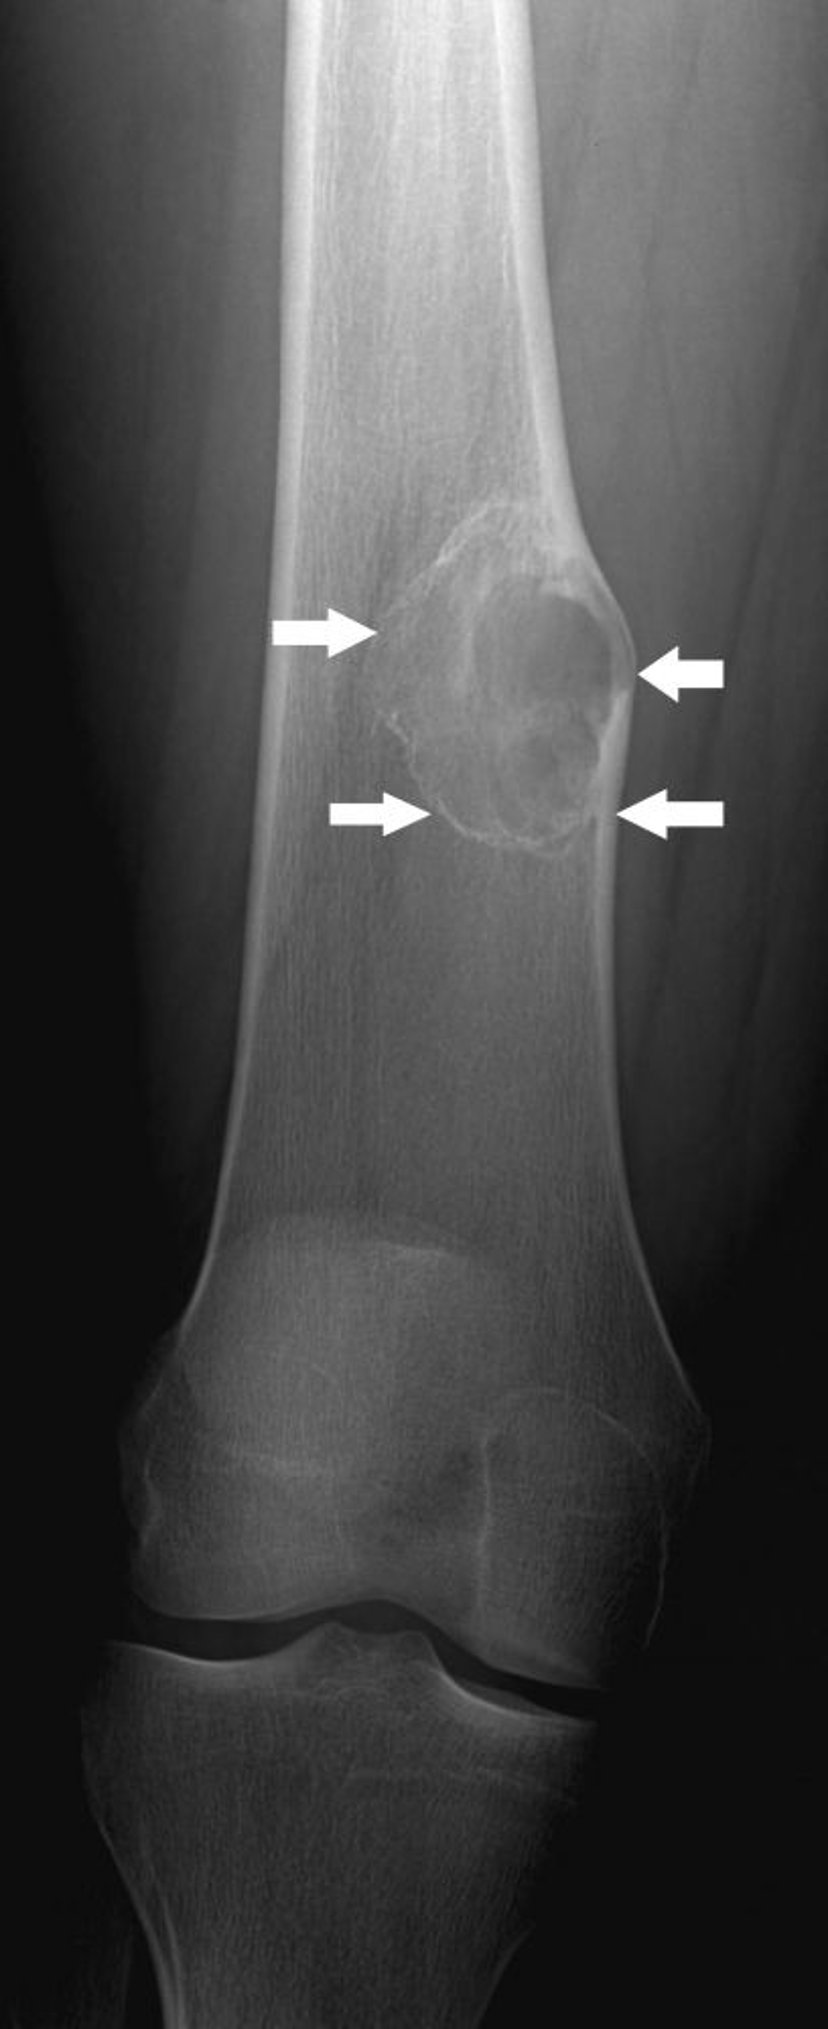

Nichtossifizierendes Fibrom

Auf dieser Röntgenaufnahme ist ein nichtossifizierendes Fibrom (Pfeile) im Oberschenkelknochen über dem Kniegelenk zu sehen.

Bild mit freundlicher Genehmigung von Dr. med. Michael J. Joyce und Dr. med. Hakan Ilaslan.